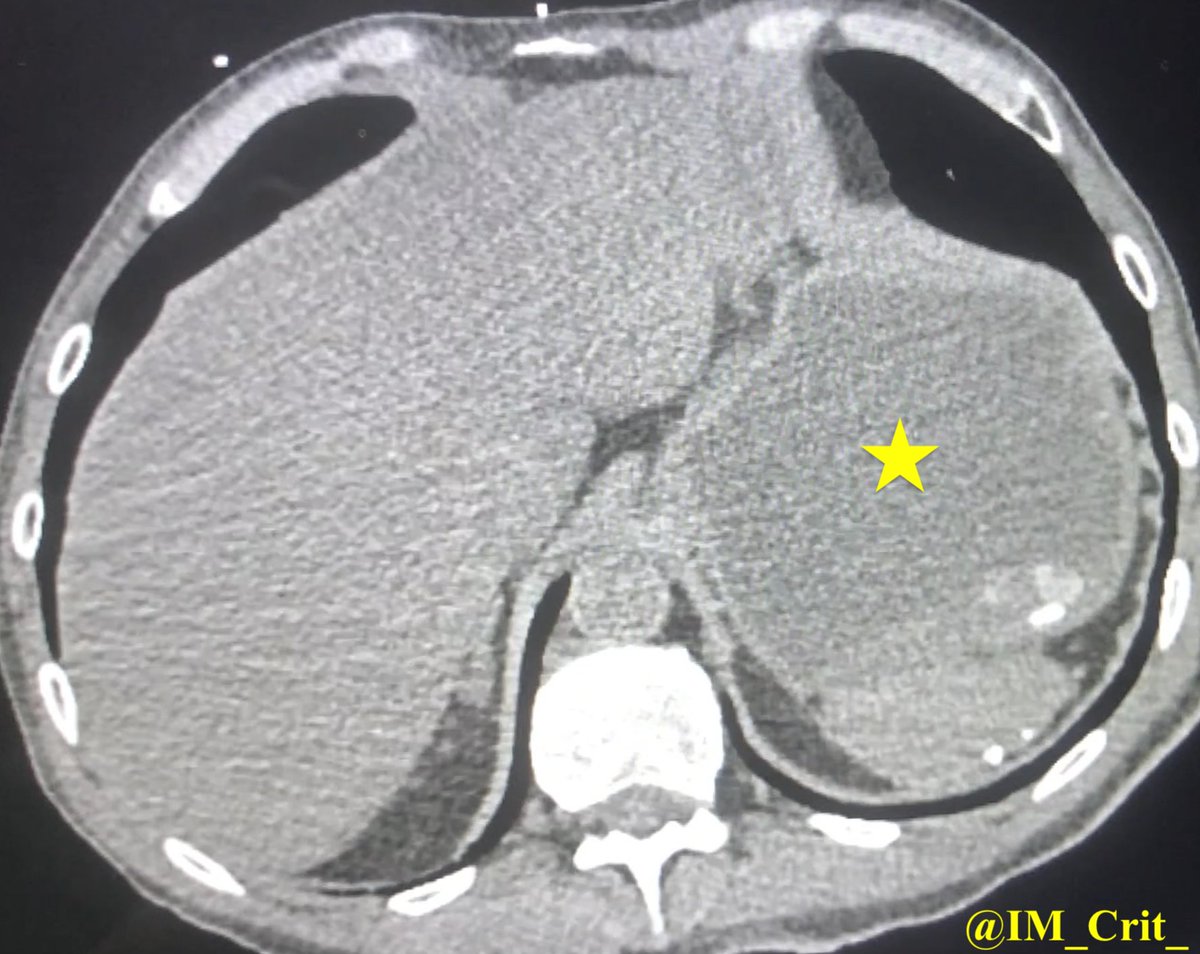

👆Interesting set of labs... . Besides the RUE weakness, patient was also very drowsy; a CT brain did not show a stroke. He received iv fluids & insulin drip. I was called to accept the patient in the ICU & in the meantime a CT was obtained and showed:

"mural thickening of multiple small & large bowel loops (nonspecific, but may be secondary to an infectious/inflammatory enterocolitis) & hepatic steatosis". Before/during the planned transfer, what would you be more concerned about?